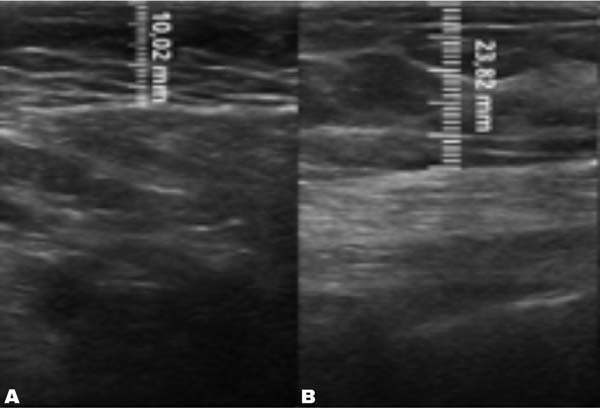

A mensuração da espessura do tecido subcutâneo é realizada de forma vertical, do ponto mais alto (logo na transição da epiderme) ao ponto mais baixo (na transição com o tecido muscular) da espessura de tecido subcutâneo. Essa medida é de fácil reprodutibilidade para quem possui aptidões básicas em ultrassonografia. ►Fig. 2. A medida da espessura de tecido subcutaneo na mama lipoenxertada foi realizada no pré- e pós-operatório imediato da lipoenxertia, e após 15,30, 90 e 180 dias. As medidas foram feitas atraves da ultrassonografia, em milimetros, medindo a distancia vertical do ponto mais superior (proximo à epiderme) ao mais inferior (proximo à musculatura adjacente) do tecido subcuta neo no ponto previamente definido. Foi utilizado equipamento de ultrassom modelo GE, LOGIQP6 (GE Healthcare) com uso de sonda linear de 11L com faixa de frequencia de 12 a 6 MHz, operado por cirurgião com pós graduação lato sensu em ultrassonografia geral. ►Fig. 3.

Fig. 3 - Ultrassonografia do grupo gordura decantada. (A) Pré-operatório com 10,02 mm de espessura de subcutâneo. (B) Pós-operatório imediato com 23,82 mm de espessura de subcutâneo

No grupo enxerto decantado, a reducãomédia, comparando-se a espessura inicial apos lipoenxertia, foi de 9,90% no 15° dia, 19,27% no 1° mes, 23,59% no 3° mes e 26,36% no 6° mes. No grupo enxerto filtrado, a reducao media, comparando-se a espessura inicial apos lipoenxertia, foi de 7,74% no 15° dia, 14,85% no 1° mes, 20,67% no 3° mes e 22,80% no 6° mes. ►Fig. 6. A evolução ao ultrassom da espessura do tecido subcutâneo antes e depois da lipoenxertia pode ser vista nas ►Figs. 7-8. Os resultados de pré-e pós-operatório de uma paciente de cada um dos grupos estão exibidos nas ►Figs. 9-10.